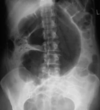

22

Small bowel obstruction